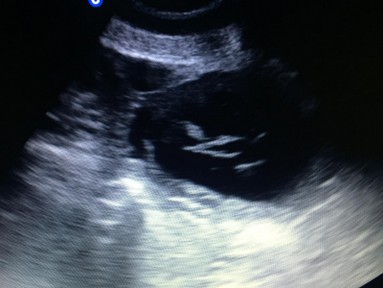

Unsere Welpen sind am 10.07.2022 geboren.

Es sind 6 Rüden und 5 Hündinnen, alle sind gesund und wohlauf.